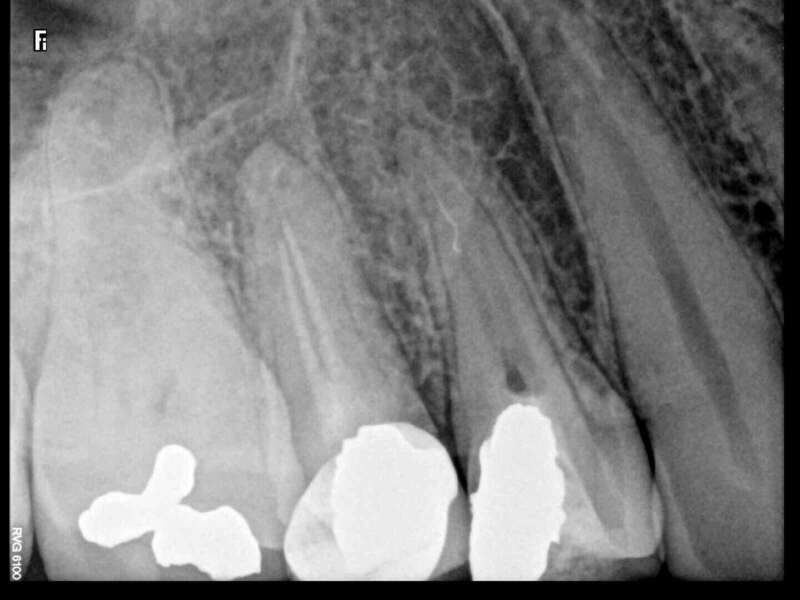

Avant